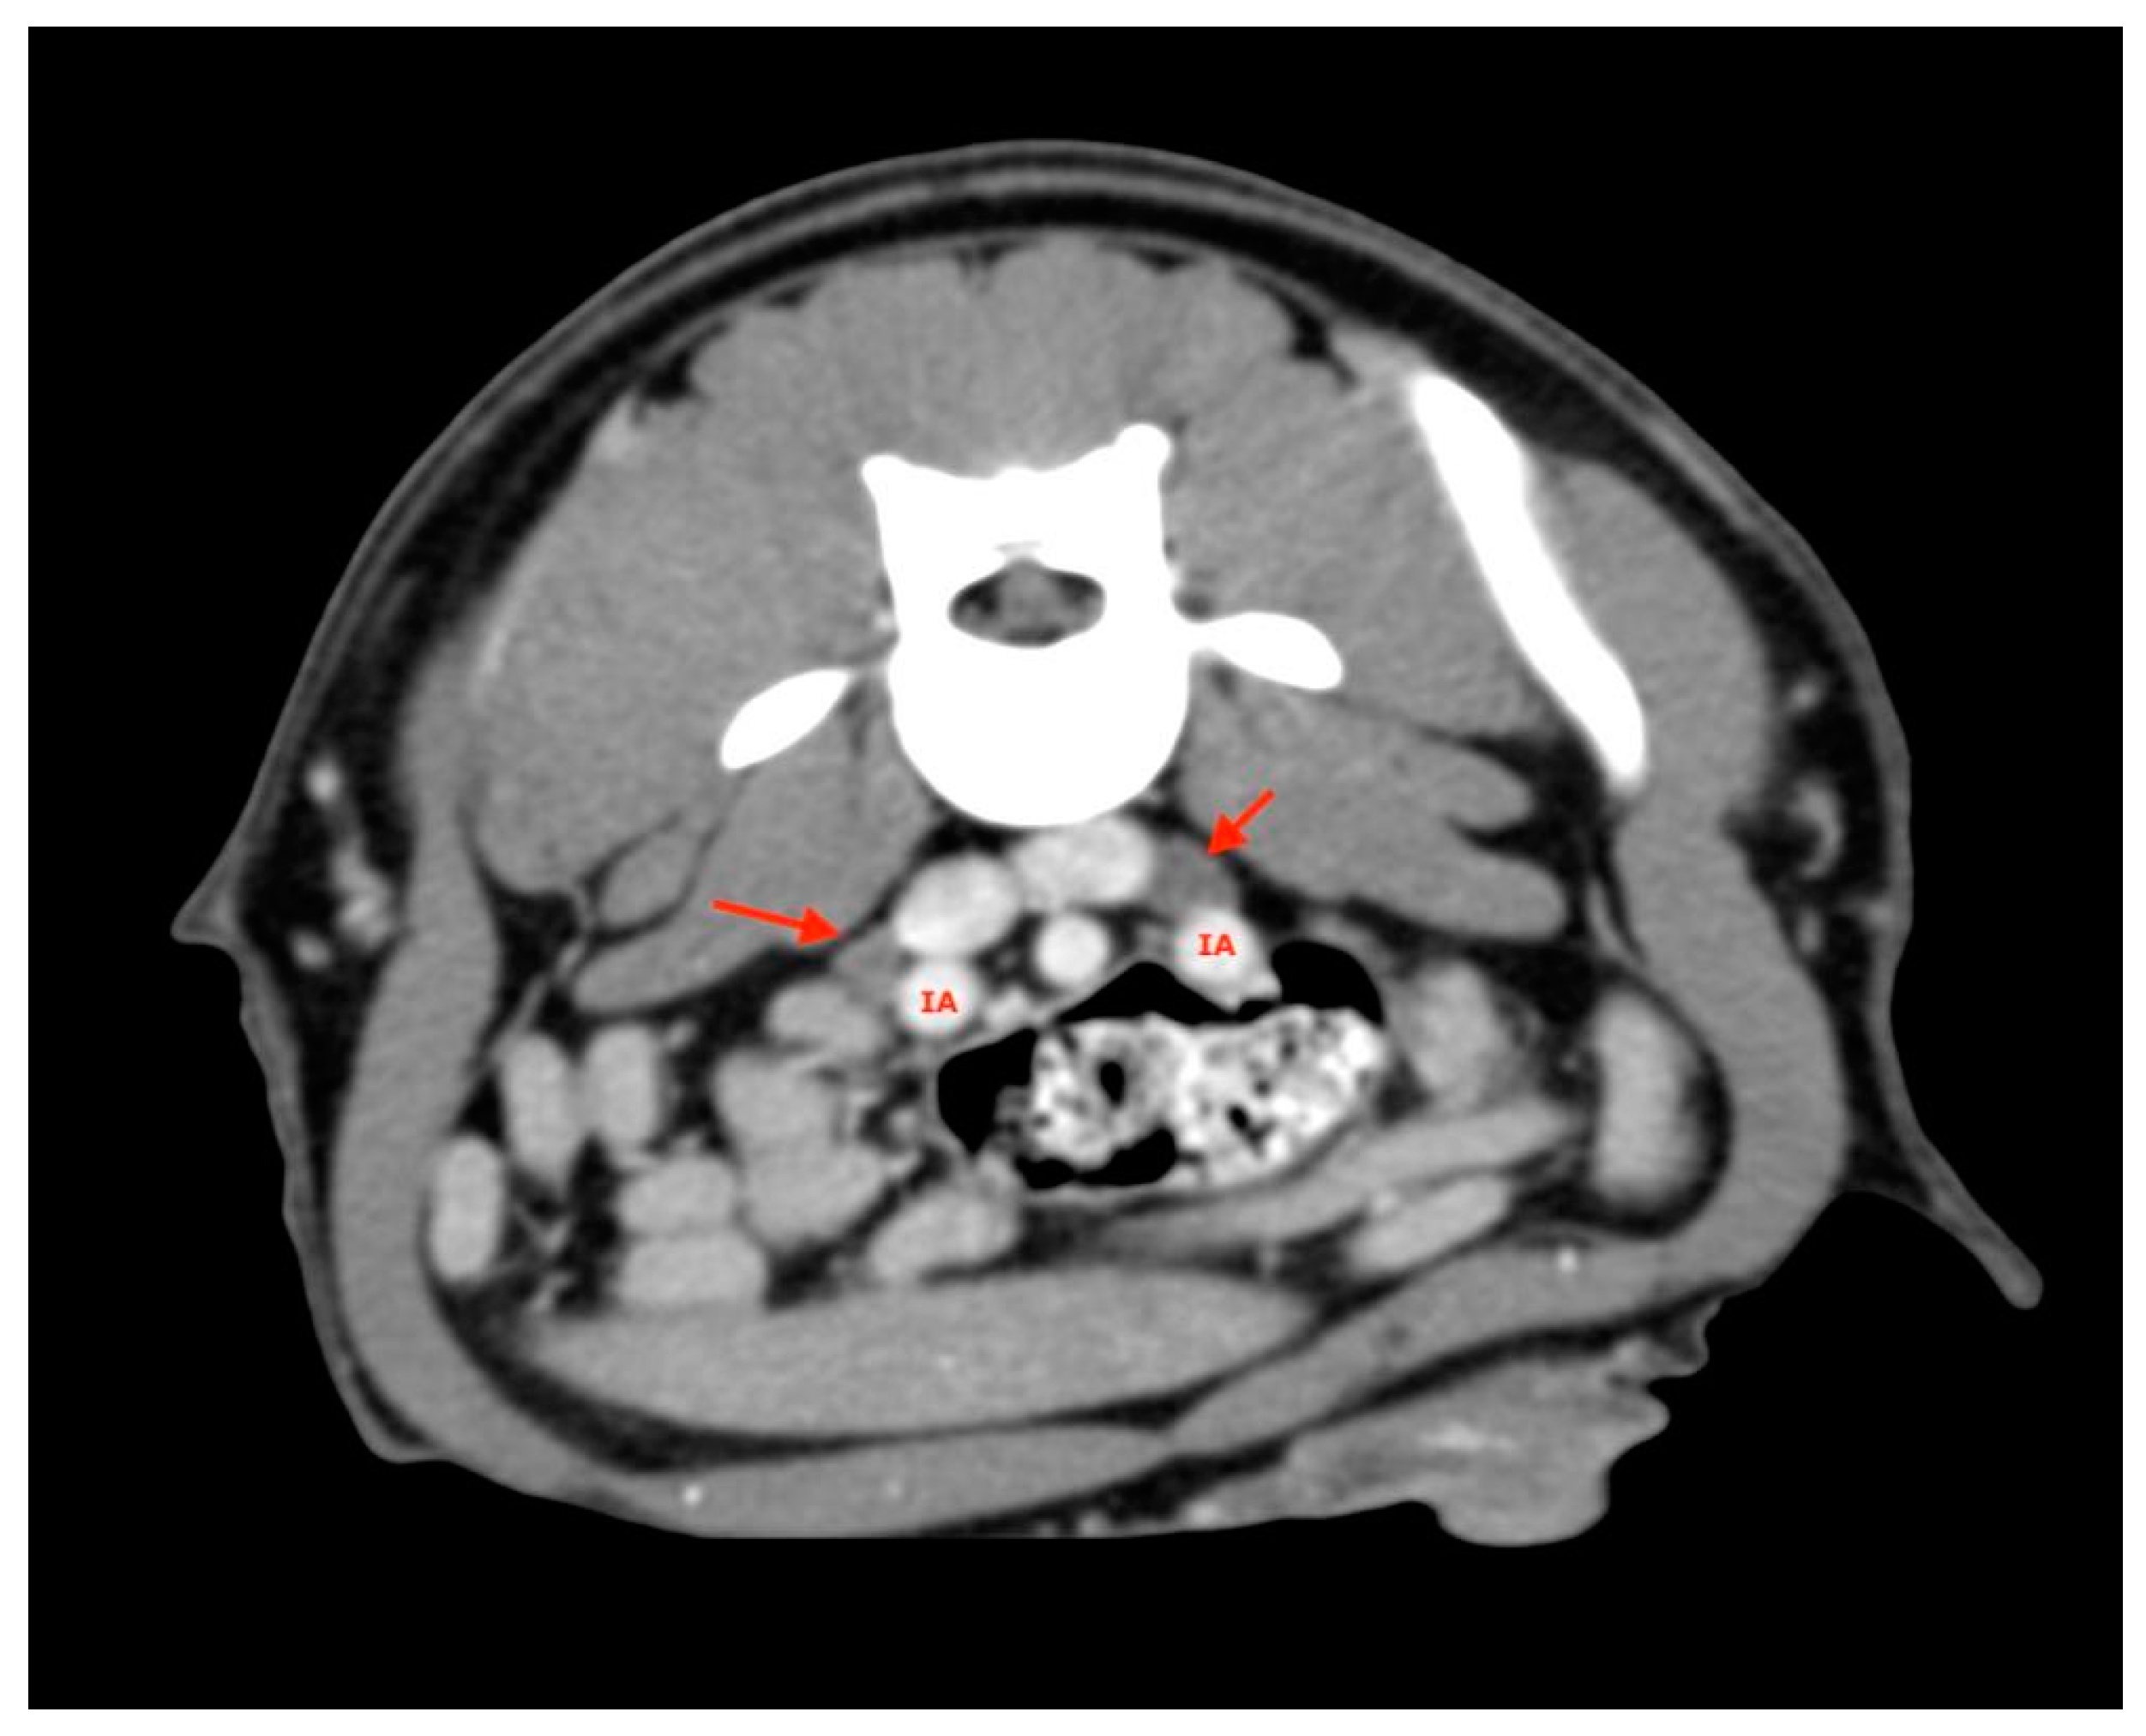

2.5. Measurements